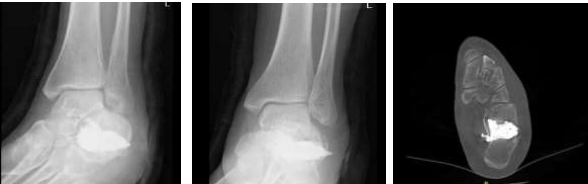

Radiographic assessment confirmed the diagnosis of an intra-articular calcaneal fracture. This was characterized by disruption of the Bohler angle and an increase in the Gissane angle, suggestive of posterior facet height loss (Figures 1 and 2). No extension into the calcaneocuboid joint was identified.

Figure 1

Figure 2